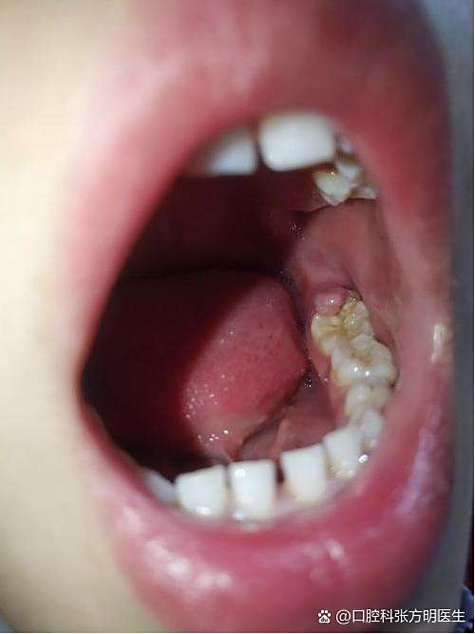

| 牙龈增生 | 牙龈组织过度生长,部分覆盖牙面或托槽,形成“假性牙周袋”,易嵌塞食物 | 长期慢性刺激(菌斑、矫治器)导致牙龈纤维组织增生 |